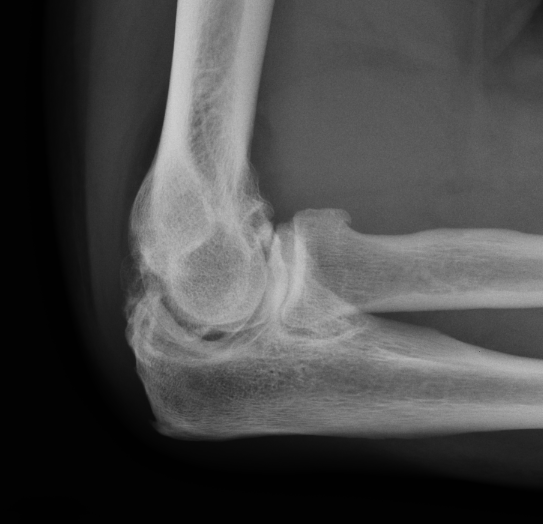

Multiple elbow loose bodies

Single loose body in adolescent

Capitellar OCD www.boneschool.com/capitellar-OCD

Elbow osteoarthritis and & stiffness www.boneschool.com/elbow-OA